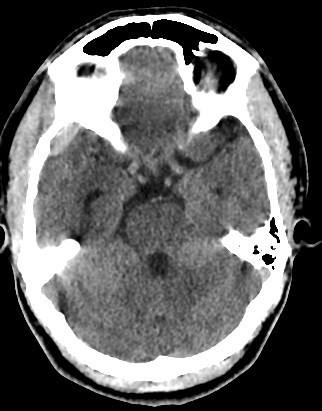

• 30 years old male with trauma

• A well-defined extraxial elliptical shape fresh blood density seen in the right fronto-parietal region.

• The lesion measured ……. cm in its maximal dimensions.

• The lesion exert little mass effect in the form of effacement of the cortical sulci and and mild midline shift.

• right fronto parietal subglial hematoma seen

• associated right fronto parital fracture seen

• no brain herniation.

• Normal size and configuration of the ventricular system.

• No intracerebral or intraventricular recent blood density.

• Normal appearance of the brain stem and cerebellum.

acute extradural hematoma with fracture

• Biconvex (lentiform) hyperdense collection adjacent to the inner table of the skull.

• Does not cross sutures (limited by dural attachments).

• Underlying skull fracture commonly visible, especially in the temporal region.

• Mass effect: midline shift, compression of adjacent sulci or ventricles.